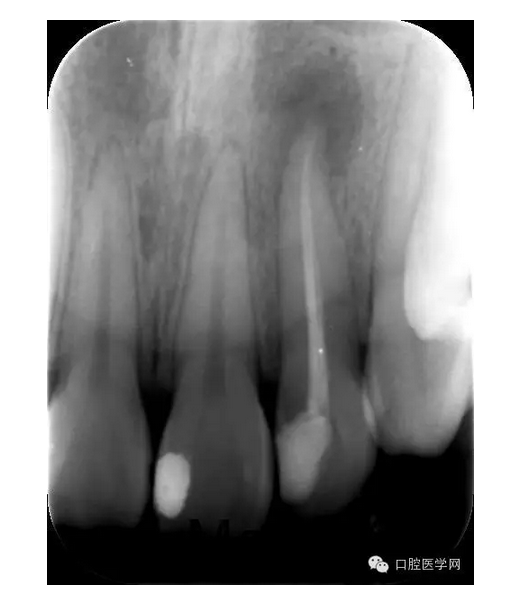

X線片:示22已行根管治療,治療不完善,根尖區(qū)可見約0.5*0.5mm密度減低區(qū),牙周膜影略增寬。

第四次:復(fù)診無不適。叩診無不適,無松動(dòng)。復(fù)查X線片,根尖密度減低區(qū)明顯減小,玻璃離子體部分去除,樹脂充填,調(diào)牙合,拋光。醫(yī)囑待18周歲后行冠永久修復(fù)。